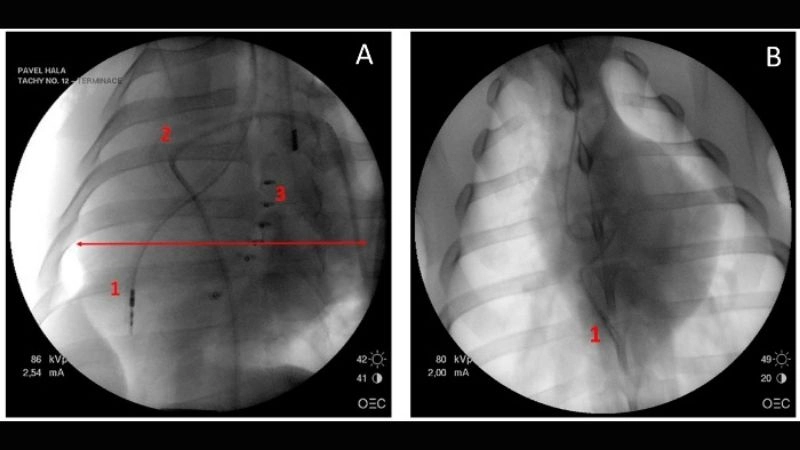

Images visual examples of Tachycardia-Induced Cardiomyopathy

Visual examples of Tachycardia-Induced Cardiomyopathy typically show an enlarged heart with weakened muscle fibers, representing reduced pumping strength and structural changes caused by chronic tachycardia.